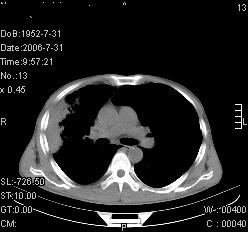

患者,男,54岁,咳嗦,咳痰20天。抗炎治疗2周。现esr76mm/h,目前患者症状明显好转,但发现两次ct片未见明显变化。两次分别做与7.25、7.31。第一次诊断右肺上叶炎症累计胸膜。大家看,从影像上内排除结核吗?

结核的可能性非常大,右上肺病变应该考虑干酪性肺炎。理由:

1.纵隔内多发淋巴结肿大。

2.esr76mm/h。

3.虽经抗炎治疗肺窗病灶有所吸收、减小,但纵隔窗病灶形态、密度、范围无明显变化。如果是单纯的大叶性肺炎,“抗炎治疗2周,目前患者症状明显好转”病灶应该基本消散了,至少也处于吸收消散期,密度变淡、范围变小。同时本病例所示其内的密度不均匀,见多发大小不一空洞样影也不符合大叶性肺炎吸收消散期表现。

病灶特点:片状 索条 结节混杂影,部分融合,密度不均,广泛累及相应胸膜.

临床治疗;二周未吸收.但症状好转.

多考虑:肺结核.